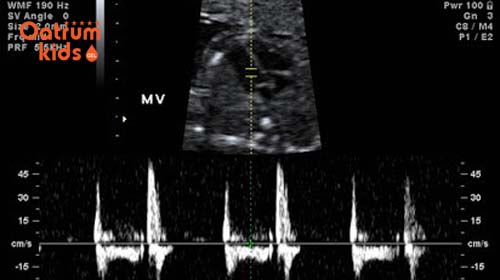

7, Nhịp tim của bé ở mức ổn định

Nhịp tim thai nhi dao động 120-160 nhịp/phút là bé đang phát triển tốt.

Theo dõi nhịp tim của trẻ cũng được xem là dấu hiệu cho thấy thai phát triển tốt. Hầu hết khi đi siêu âm các bác sỹ sẽ kiểm tra tim thai và cho mẹ nghe tim thai đầu tiên. Nhịp tim trung bình của bé sẽ dao động khoảng tầm 120 đến 160 nhịp đập/phút, nhịp tim này cũng có thể thay đổi theo từng giai đoạn, có khi 140 hay 150 nhưng nhìn chung là vẫn dao động khoảng 120-160 nhịp/phút. Do đó nếu em bé của bạn khi đi siêu âm mà luôn nằm trong ngưỡng này thì có thể an tâm con đang phát triển khoẻ mạnh nhé.